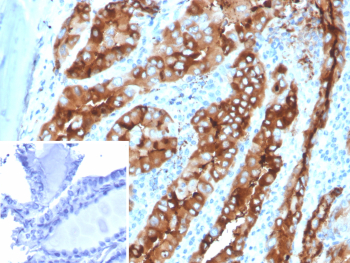

Immunohistochemistry analysis of Thyroid Globulin / TG antibody in human thyroid tissue (clone TGB/4582R). FFPE human thyroid sections demonstrate strong HRP-DAB brown cytoplasmic staining in follicular epithelial cells, with intense brown chromogenic signal filling the follicular lumina corresponding to colloid material. The staining pattern is consistent with abundant Thyroglobulin synthesis and secretion by differentiated thyroid follicular cells. Surrounding stromal elements show minimal staining. The inset shows PBS used in place of primary antibody as a secondary antibody negative control, confirming absence of specific brown chromogenic signal. Heat induced epitope retrieval was performed in 10 mM Tris with 1 mM EDTA, pH 9.0, by heating tissue sections at 95oC for 45 minutes followed by cooling at room temperature for 20 minutes prior to antibody incubation.